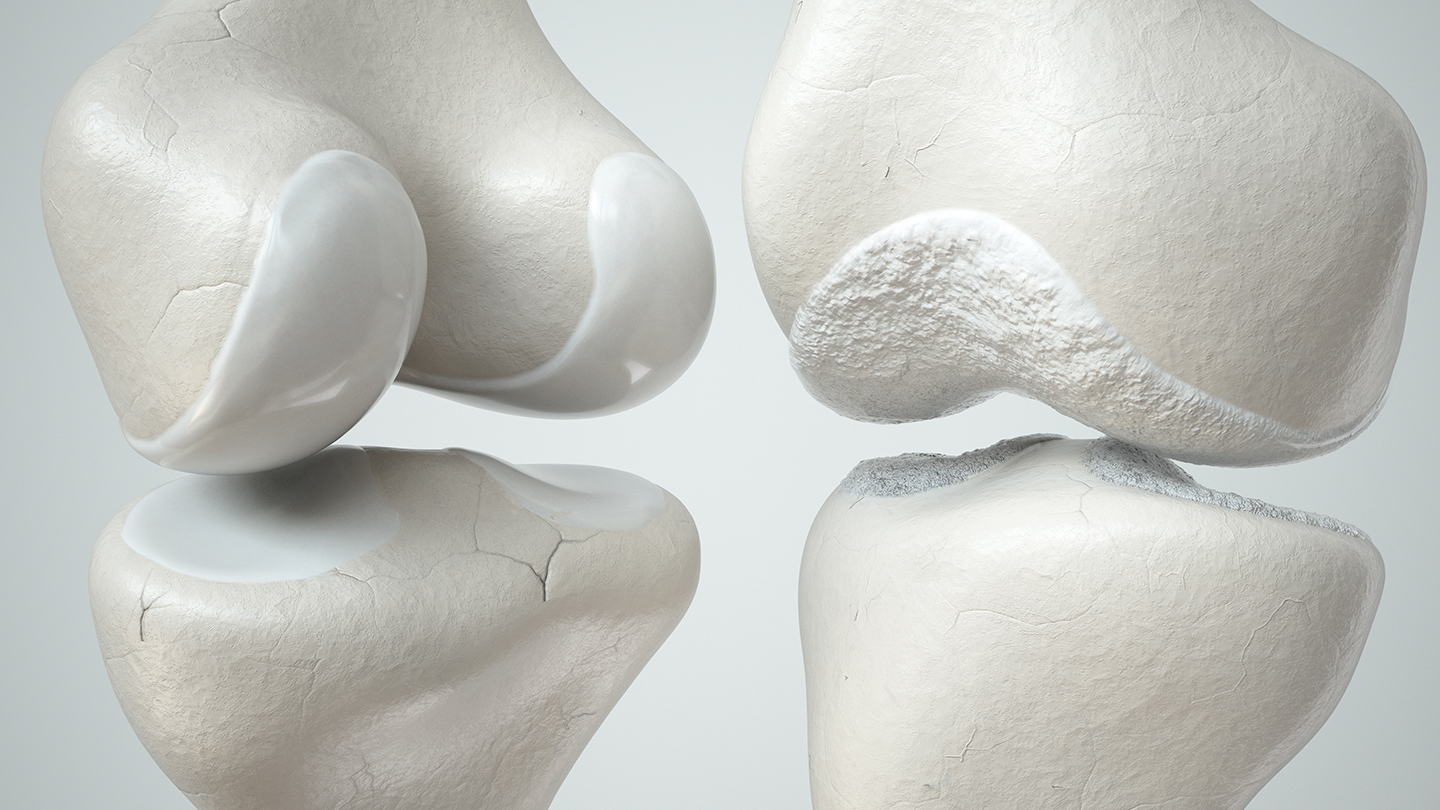

För många som har problem med sina leder kan besvär som daglig obehag, smärta eller till och med något mer allvarligt som artros göra att dessa vardagliga rörelser känns som en ständig kamp.

Den moderna mikronäringsterapin använder kunskapen om de enskilda näringsämnenas effekter för att utveckla kosttillskott baserade på kollagen. Det naturliga strukturproteinet är en huvudkomponent i bindväv, ben, hud och brosk och fungerar som en slags stötdämpare för dina leder.

Värkande leder behöver inte alltid bero på en allvarlig orsak; ofta är det en felaktig livsstil som ligger bakom ledproblemen. Felaktiga belastningar, en ohälsosam kost med få mikronäringsämnen, övervikt och för lite motion kan främja besvär med lederna.

För att förebygga de skador som kan uppstå, vilka ibland kan vara irreversibla, bör fokus ligga på en ledvänlig kost, ergonomiska rörelser och en normal kroppsvikt.

Fakta 3: Kollagen från äggskalsmembran för att stödja broskregeneration

Ja, din kropp kan skapa nytt broskvävnad igen!

Efter att inflammationen i leden har läkt behöver kroppen rätt näringsämnen för att effektivt regenerera brosket. Men det krävs ett specifikt kollagen – det som finns i äggskalsmembran – som är en av de viktigaste byggstenarna för broskreparation och avgörande för att återuppbygga broskmatrixen. (5)

Denna källa till kollagen är nödvändig för att stödja brosket och bibehålla dess struktur.